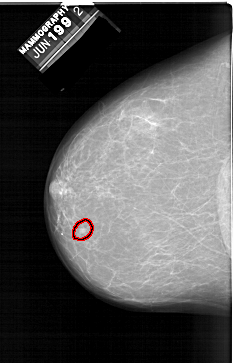

FILE: A_1398_1.LEFT_CC.OVERLAY TOTAL_ABNORMALITIES 1 ABNORMALITY 1 LESION_TYPE MASS SHAPE LOBULATED MARGINS CIRCUMSCRIBED ASSESSMENT 3 SUBTLETY 3 PATHOLOGY BENIGN TOTAL_OUTLINES 1 BOUNDARY |